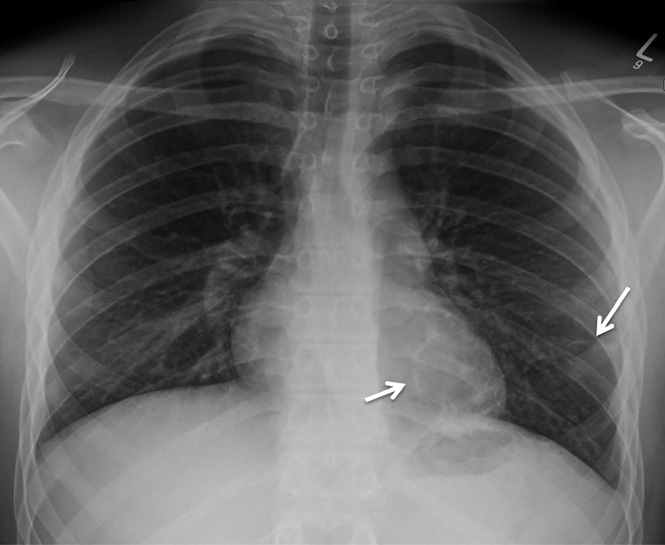

患者支氣管鏡檢查無明顯異常,未見支氣管內(nèi)病變。支氣管肺泡灌洗檢查無抗酸桿菌、細(xì)菌、真菌,分枝桿菌培養(yǎng)物中無病原體生長?;颊呓?jīng)過14天的哌拉西林/他唑巴坦治療出院。出院8周后復(fù)診,胸部X線顯示實(shí)變和氣液平面消退,但左肺下葉發(fā)現(xiàn)兩個(gè)殘留的薄壁空洞(圖3)。

圖3 左肺下葉發(fā)現(xiàn)兩個(gè)殘留的薄壁空洞(實(shí)線箭頭)